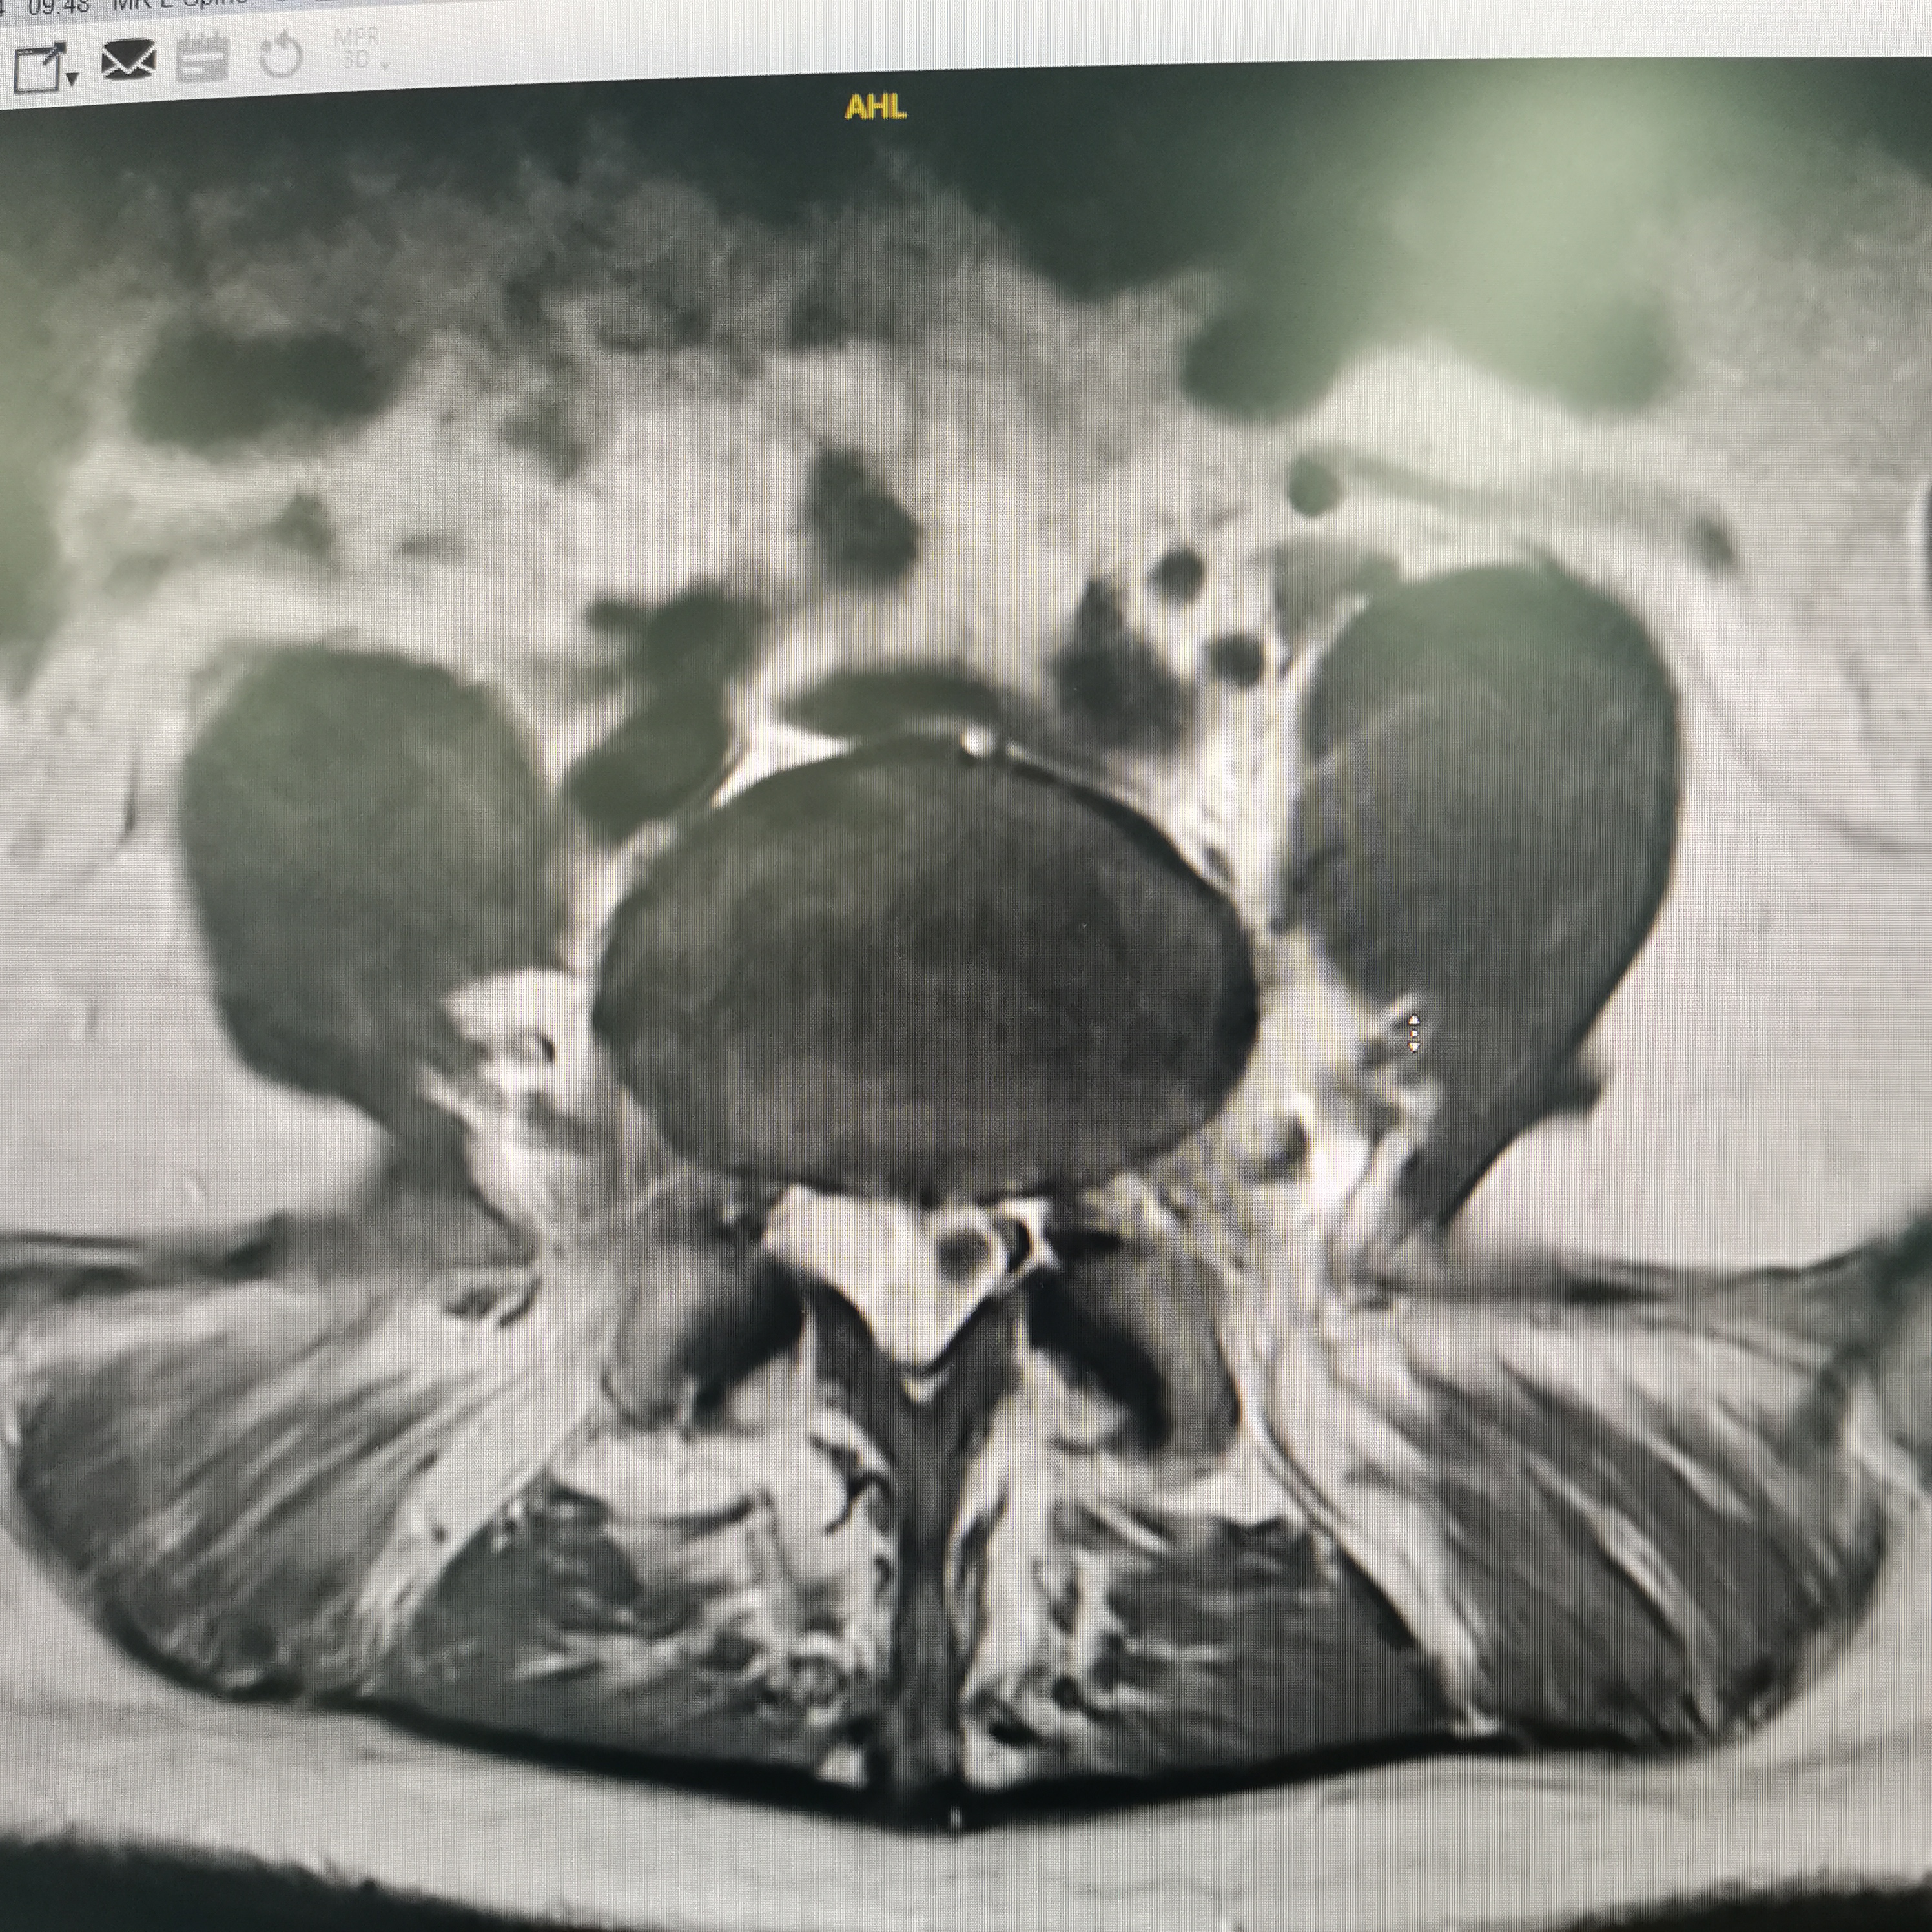

膝关节疼痛,原因是椎管内肿瘤,哑铃型生长,全切肿瘤,保留神经,疼痛症状消失…